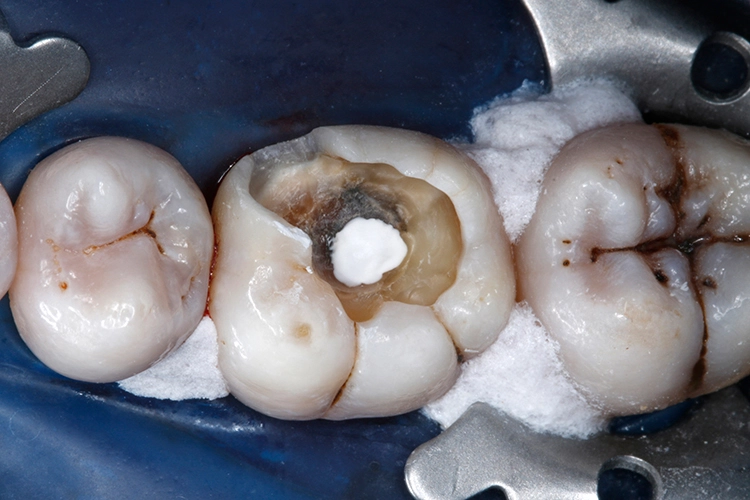

Ein 38-jähriger Patient erschien in unserer Sprechstunde mit einem frakturierten mesiolingualen Höcker neben einer okklusalen Amalgamfüllung am unteren rechten 1. Molaren (Zahn 46). Der Vorfall hatte sich bereits vor einer Woche ereignet, der Zahn war noch am selben Tag im zahnärztlichen Notdienst provisorisch mit einer Glasionomerzementfüllung versorgt worden (Abb. 1). Der Defekt erstreckte sich bis auf Höhe der marginalen Gingiva (Abb. 2).

Anschließend wurden sämtliche Kavitätenränder mit einem Feinkorndiamanten nachgearbeitet und finiert. Danach wurden die pulpanahen Kavitätenareale mit einem selbstlimitierenden Polymer-Rosenbohrer (Polybur, Gebr. Brasseler GmbH & Co. KG, Lemgo) substanzschonend exkaviert (Abb. 7), eine Exposition der Pulpa konnte mit diesem Vorgehen der selektiven Exkavation vermieden werden (Abb. 8) [51–55]. Das pulpanahe Dentin im Zentrum der Kavität wurde mit einer dünnen Schicht röntgenopaker Calciumhydroxidpaste auf wässriger Basis (Calcicur, VOCO) indirekt überkappt (Abb. 9). Das Calciumhydroxidpräparat wurde mit einer partiellen Unterfüllung aus lichthärtendem kunststoffmodifiziertem Glasionomerzement (Ionoseal, VOCO) abgedeckt (Abb. 10).